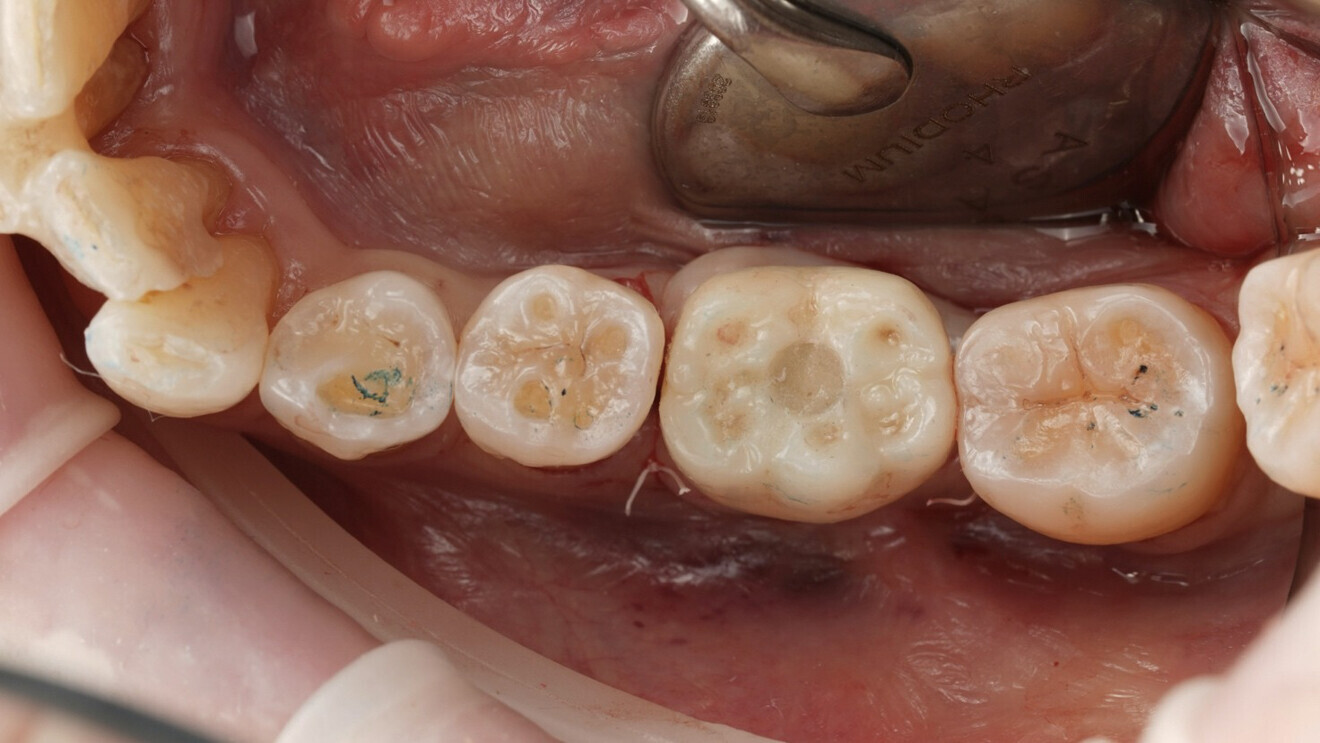

Fig. 2: Intra-oral scan of the mandibular arch.

Digital planning and preoperative prosthesis fabrication A digital workflow was started with the acquisition of intra-oral scans of the maxillary and mandibular arches using the ViSIOScan WL wireless scanner (Cefla; Fig. 2). The STL files were aligned with the CBCT data in RealGUIDE software (3DIEMME), which allowed prosthetically guided planning of the implant position (Fig. 3).